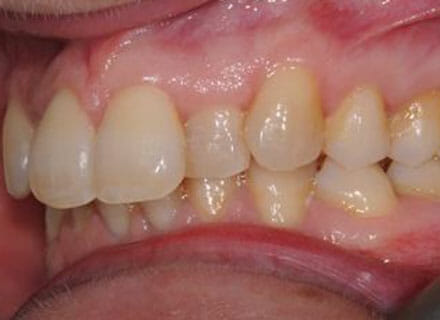

In this case, we needed to reduce the size of the central incisors as they were just too big. This combined with the crowding at the front had caused the lateral incisors to become trapped inside, pushing the big central incisor teeth forwards even more. After reducing the big teeth to a normal size we started with fixed clear bracket brace treatment and were able to complete this case in a little over a year.